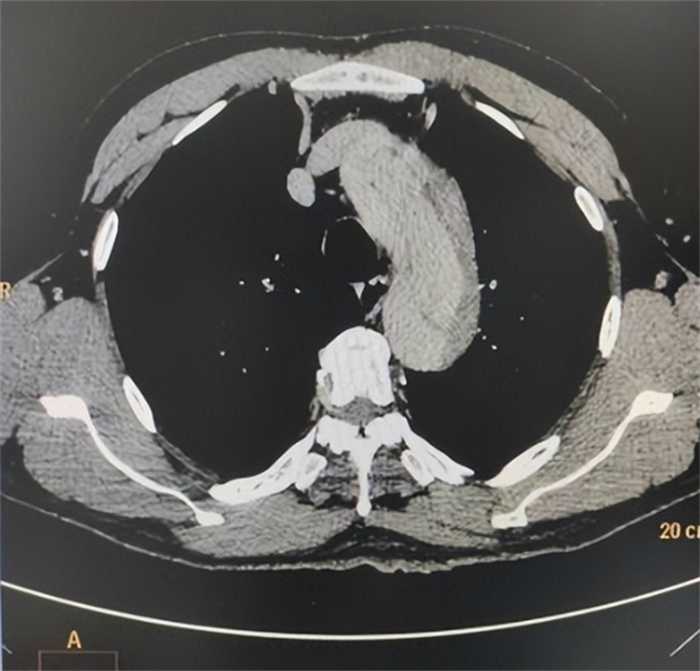

医生对单书玲进行了全面的检查,特别是进行了CT扫描,结果让医生们感到震惊。单书玲被诊断出患有主动脉夹层,这是一种心血管疾病,其短时间内的死亡率极高。

主动脉夹层是由高血压、先天性心脏病等因素引起的,它会导致主动脉内膜层撕裂,使血液从撕裂处进入主动脉中膜,形成脆弱的夹层壁。如果不及时治疗和手术,夹层壁可能会破裂,造成严重的后果,甚至危及生命。

对于患有主动脉夹层的病人来说,60%以上的人在两周内就会死亡,而剩下的40%也很少能够活过一年。因此,当医生们了解到单书玲的病情后,称她为一个真正的“奇迹”。